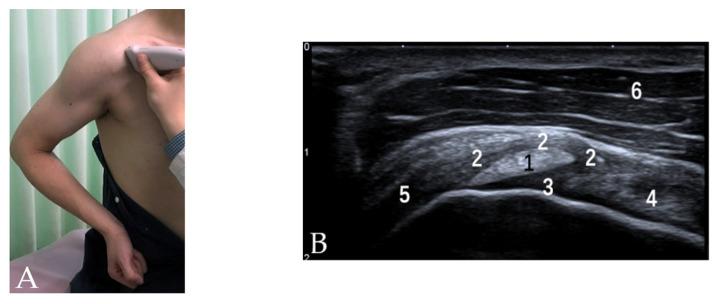

肱二头肌长头肌腱(LHBT)已被公认为是引起肩部前方疼痛的重要原因,会导致肩部屈曲范围显著减小。各种肌腱和韧带结构在LHBT走行过程中形成其锚定装置,以在肩部运动期间维持其适当位置,包括喙肱韧带(CHL)、肩胛上盂肱韧带(SGHL)、肩胛下肌(SSC)肌腱和冈上肌(SSP)肌腱,以及不太为人所知的胸大肌(PM)、背阔肌(LD)和大圆肌(TM)肌腱。该稳定装置的损伤可能导致LHBT不稳定,从而引起肩部前方疼痛。超声检查(US)已越来越多地用于评估肩部损伤,包括LHBT的锚定装置。鉴于解剖结构复杂且病理情况多样,对这些损伤进行准确诊断往往具有挑战性。在这篇综述文章中,将讨论US解剖结构以及影响LHBT锚定装置的常见病理状况,包括肱二头肌滑车损伤、粘连性关节囊炎、SSC和SSP肌腱的慢性病变、PM肌腱撕裂以及LD和TM损伤。了解正常解剖结构、合适的扫描技术以及常见病理状况的US表现是准确诊断的关键。